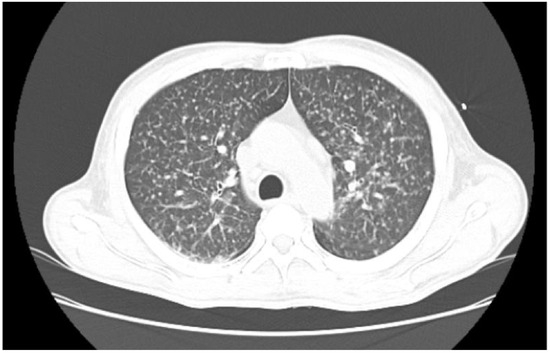

A lung computed tomography (CT) scan revealed a miliary pattern (Figure 1). M. tuberculosis was confirmed via real-time polymerase chain reaction (RT-PCR) GeneXpert® and Mycobacterial Growth Indicator Tube (MGIT) culture testing on sputum. Abdominal CT scans revealed an 18-cc abscess affecting the prostate and the right seminal vesicle (Figure 2). Urine culture and RTPCR for Chlamydia trachomatis and Neisseria gonorrhoeae were negative. Transurethral drainage of the prostatic abscess was performed, and RTPCR of the sample identified M. tuberculosis confirming the diagnosis of a tuberculosis prostate abscess. Susceptibility of M. tuberculosis to rifampin by RT-PCR was documented.

Figure 1. Axial thorax CT-scan: Miliary tuberculosis pattern of the lungs.